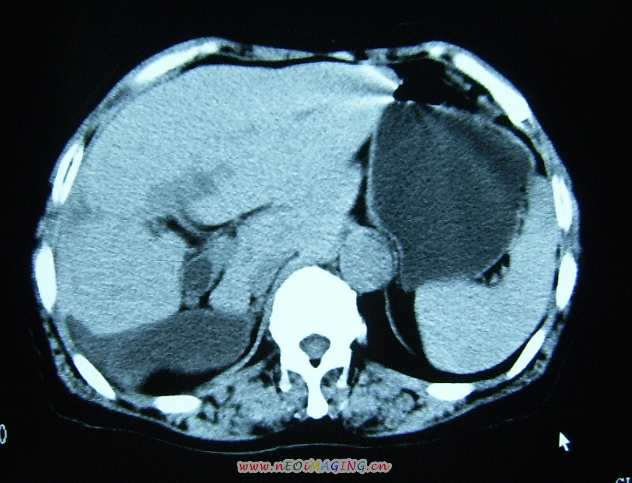

标题: CL0653:【】异位胆囊 [打印本页]

标题: CL0653:【】异位胆囊

女56y右上腹不适数年.

支持,我也遇到过一例后位胆囊。

支持;还有肝内异位的。

异位胆囊